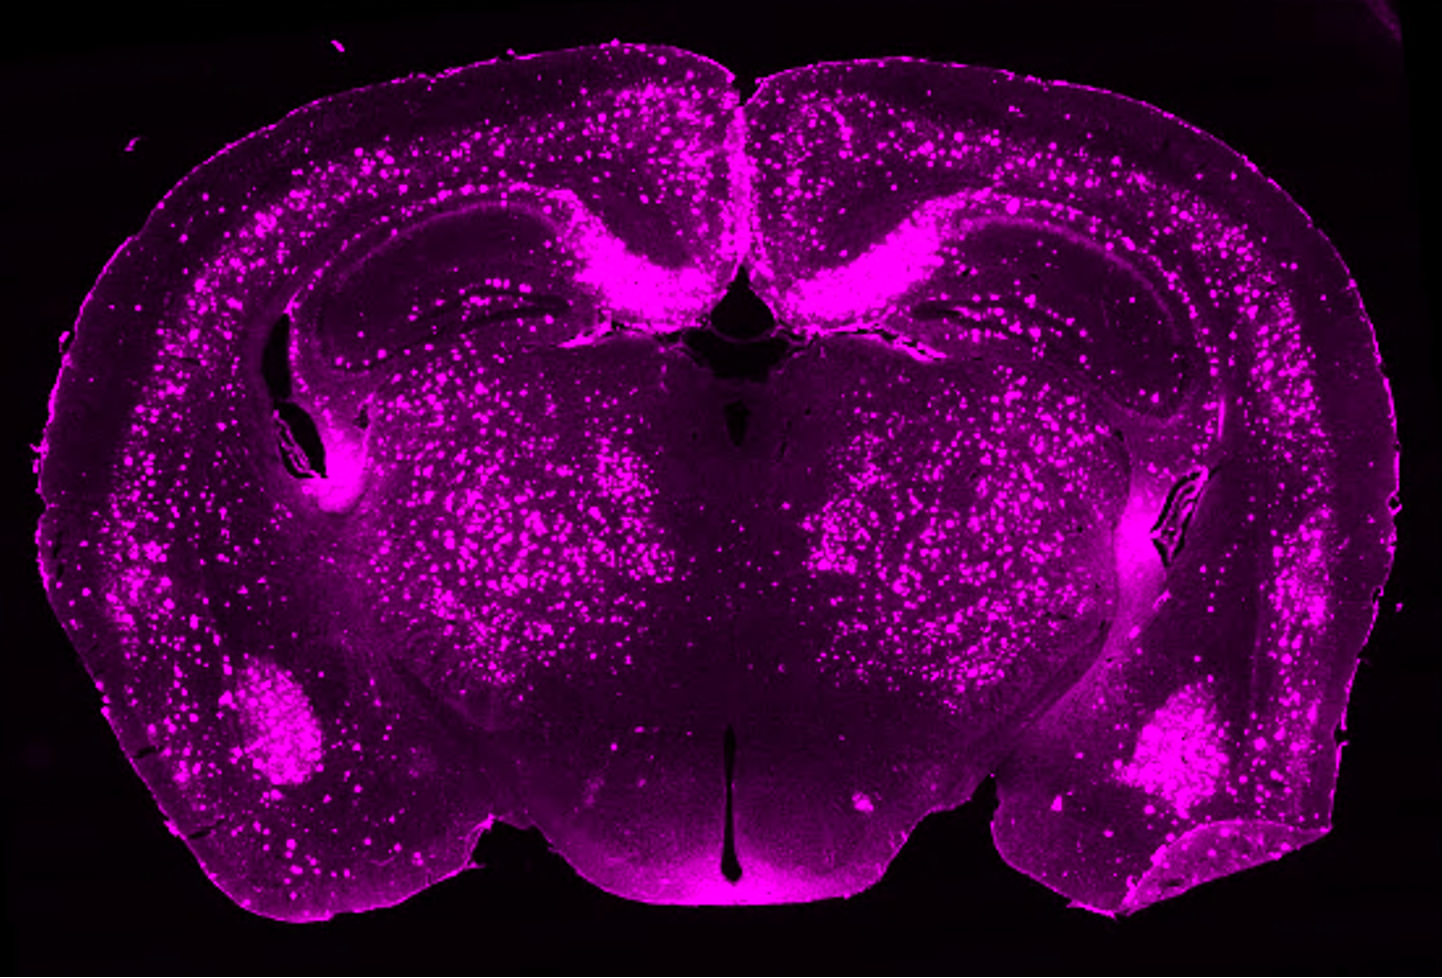

Her research focuses on the glymphatic system, a brain-wide network of perivascular pathways and aquaporin-4 (AQP4) water channels, that facilitates the exchange of fluid throughout the brain and is important for the transportation and clearance of solutes and brain waste. Glymphatic system dysfunction occurs in normal aging as well as many neurological disorders, such as Alzheimer's disease, Parkinson’s disease, stroke, traumatic brain injury, and cerebral small vessel disease.

Current projects in the lab are examining neutrophil extracellular trap-induced glymphatic dysfunction in Alzheimer’s disease and menopause-induced glymphatic dysfunction as a possible risk-factor for Alzheimer’s disease. The Braun lab is also examining differences in localization of AQP4 water channels across mammalian species with varying levels of cortical folding and how this may impact glymphatic function.

During her postdoctoral work, Dr. Braun examined how loss of perivascular aquaporin-4 (AQP4) localization impaired glymphatic function and promoted amyloid pathology, using both human post-mortem brain tissue and a double transgenic mouse model (Alzheimer’s Res Ther 2022). She also examined how AQP4 mislocalization impairs glymphatic clearance of alpha-synuclein (bioRxiv 2024) and tau pathology (in prep). Current projects in the Braun lab are continuing in this line of investigation, examining mechanisms of glymphatic dysfunction in Alzheimer’s disease.